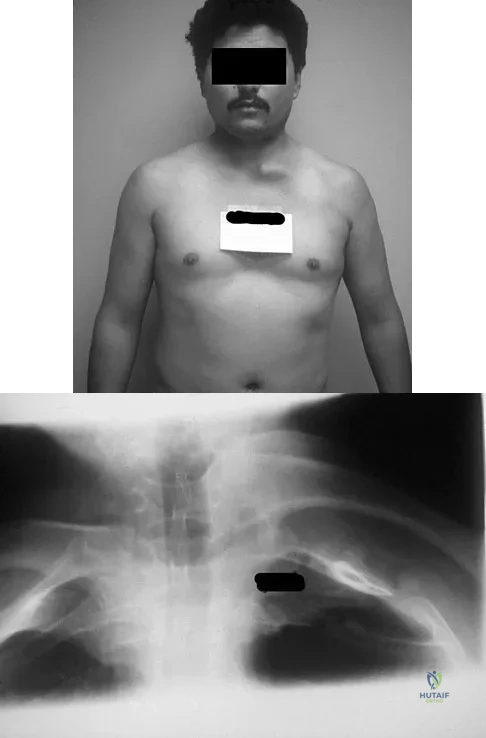

Question 65

A 42-year-old patient undergoes resection of the medial clavicle for painful sternoclavicular degenerative joint disease. The postoperative course is complicated by an increase in symptoms, a medial bump, and subjective tingling in the digits. A clinical photograph and radiograph are shown in Figures 20a and 20b. What is the most appropriate procedure at this time?

Explanation